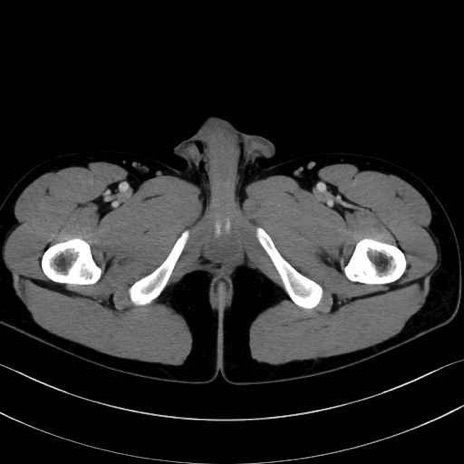

内閉鎖筋 (Obturator internus)